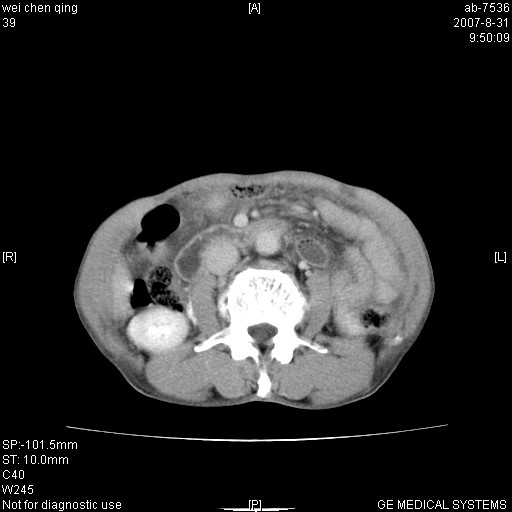

以下是引用zyyzzy在2007-8-31 14:34:00的发言:[br]该病人肝内胆管扩张,胆囊及胆总管未见明显扩张。在倒数第9层图像上可看到左右肝管结合部(肝总管)有软组织影,此处应薄层扫描。考虑肝总管占位(ca)、腹水。[br]